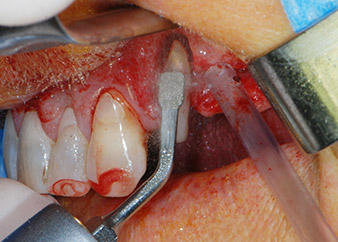

Un mois plus tard, le jour de l'intervention, la douleur et l'inflammation sur la dent 24 étaient minimes mais une mobilité de classe 2 de Miller était toujours observable. Après ouverture des lambeaux et nettoyage des tissus périapicaux et périradiculaires infectés, l'étendue du défaut osseux est devenue parfaitement visible (Figures 2 et 3).

À la racine de la dent, il manquait la totalité de l'os vestibulaire et distal. L'attache était essentiellement limitée à la racine palatine, venant ainsi confirmer le pronostic défavorable initial. La dent 27 présentait également une attache horizontale réduite et une raréfaction apicale minime (cf. Fig. 1), sans symptômes cliniques.

Nous avons toutefois maintenu notre projet initial de conservation des deux dents comme piliers temporaires d'un bridge pendant la période de six mois nécessaire à l'ostéointégration des implants. À la prochaine incision, la situation devrait être réétudiée. Premièrement, afin de gérer le problème endoparodontal, la surface de racine restante a été soigneusement débridée à l'aide d'un équipement piézoélectrique (Piezomed, W&H, utilisé avec l'insert en forme de spatule S1, initialement conçu pour limer la paroi sinusienne latérale) (Fig. 4).